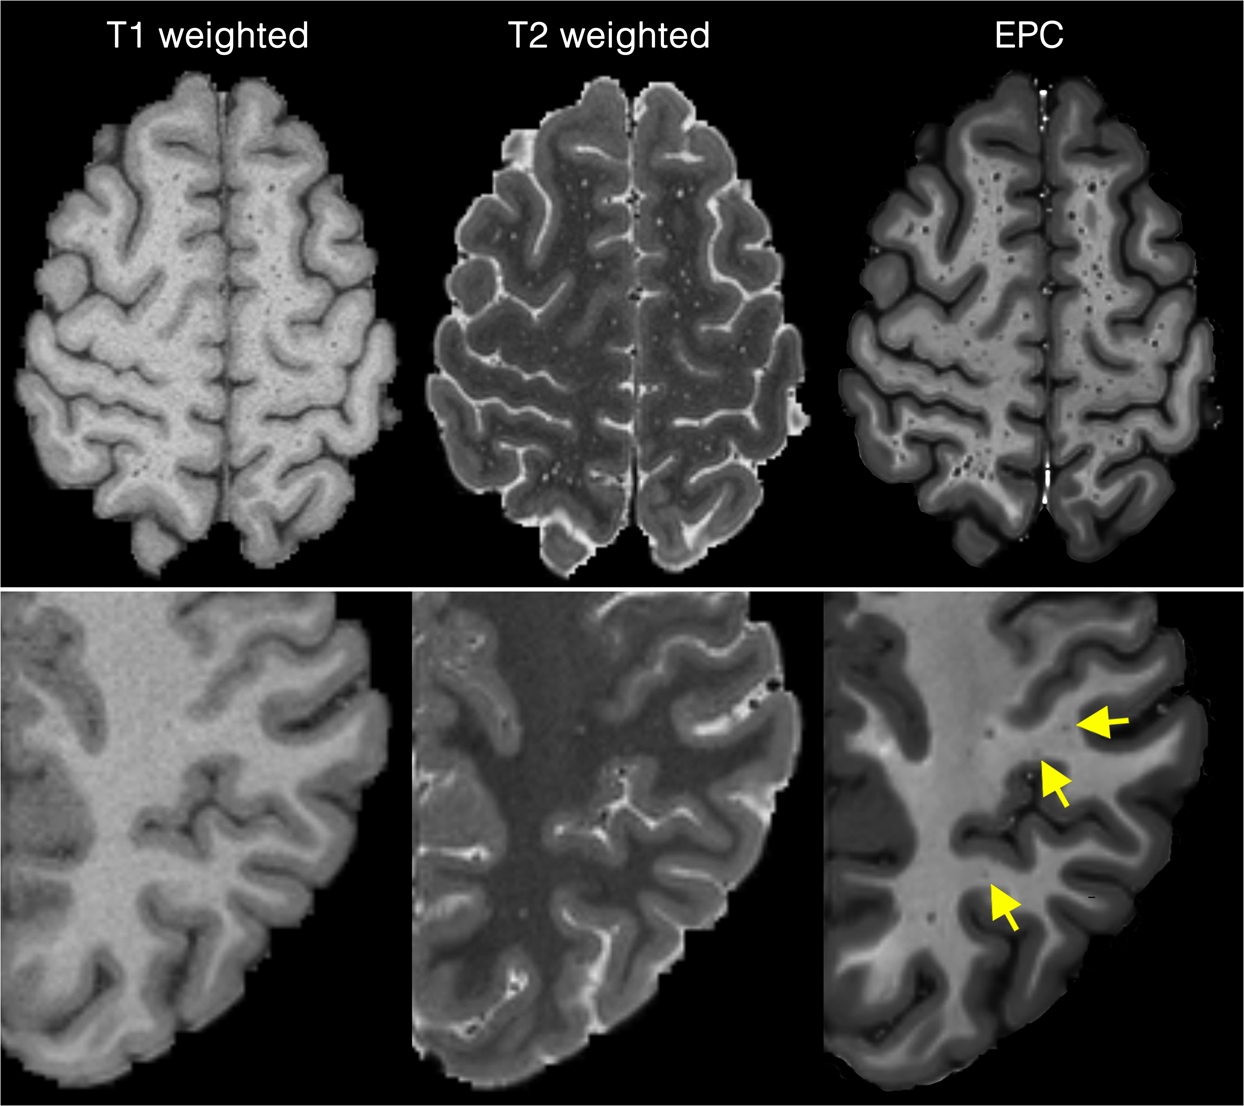

Figure 2

From: Image processing approaches to enhance perivascular space visibility and quantification using MRI

Comparing Enhanced PVS Contrast (EPC) with T1w and T2w images across two subjects with high perivascular spaces (PVS) presence (first row) and low PVS presence (second row).